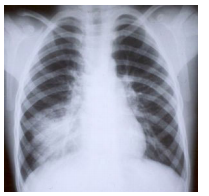

A radiografia de tórax mostra: